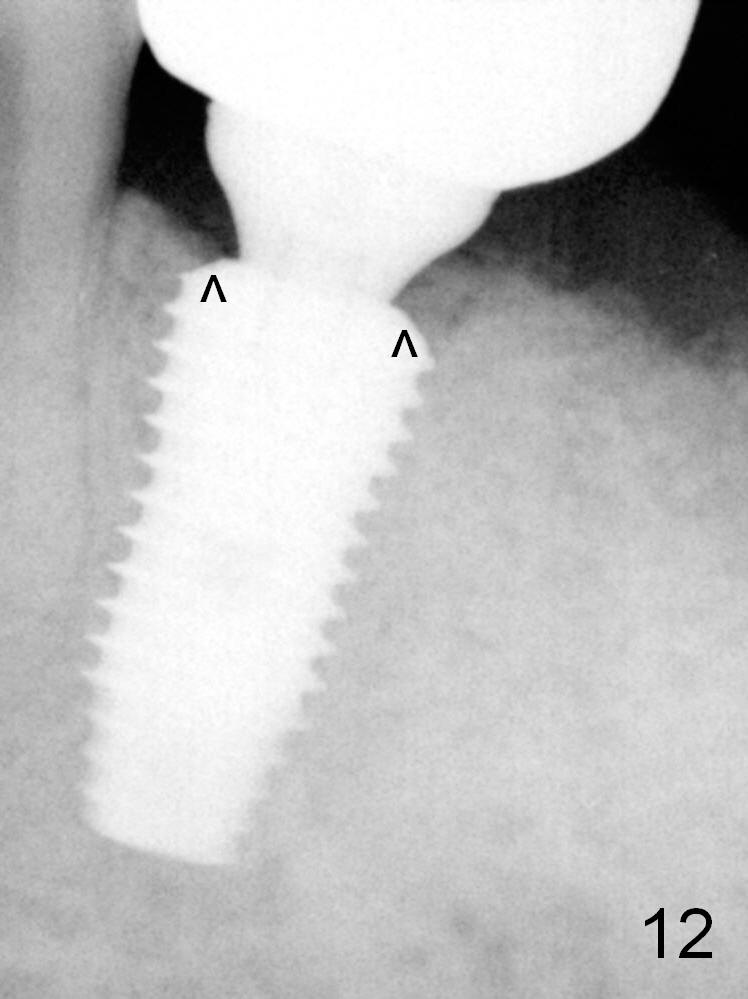

Eight months later (1 year postop (#19)), the tooth #18 becomes symptomatic and is extracted and replaced by an implant (Fig.12).  The distal socket at #19 has disappeared, while the plateau of the implant is covered by the bone (^).